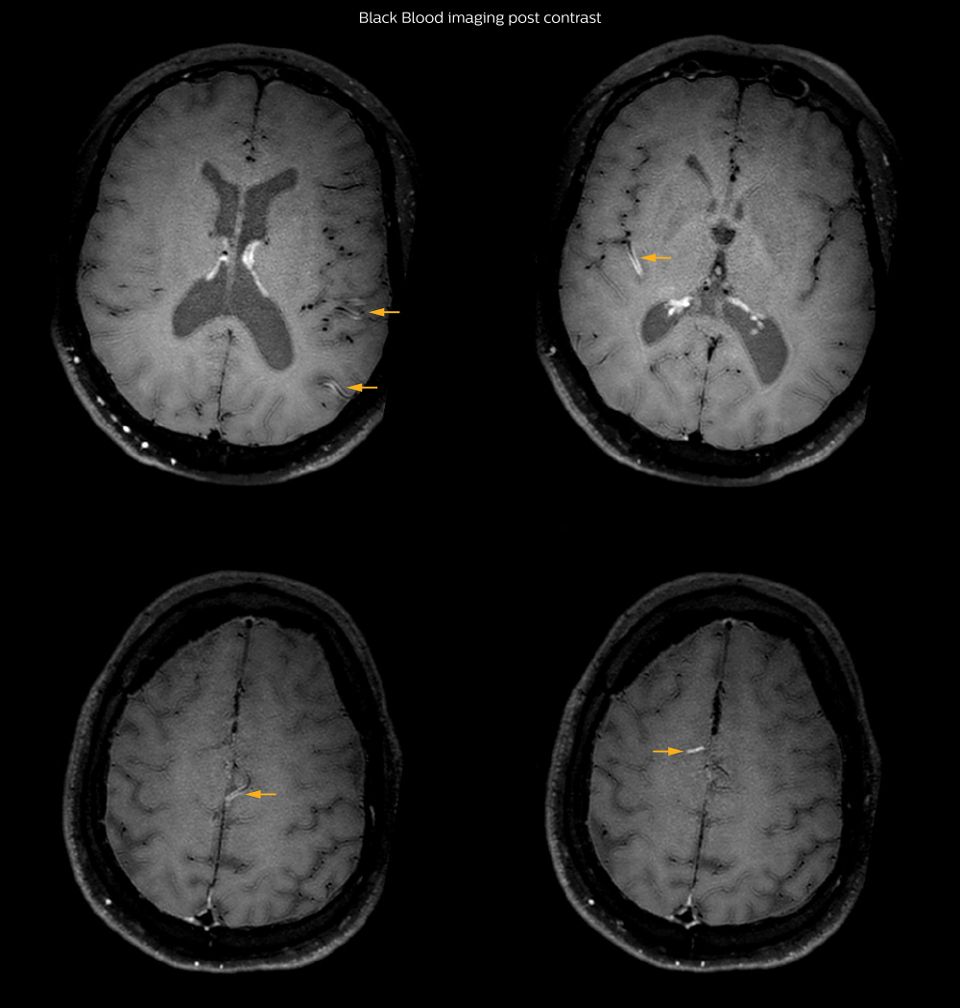

On FLAIR images we can see some nonspecific high signal abnormalities in frontal white matter bilaterally. On DWI we can see acute ischemic lesions which appear with high signal intensity. Arrows show vessel wall enhancement which appears concentric and homogeneous in different cerebral territories.

Arrows show vessel wall enhancement which appears concentric and homogeneous in different cerebral territories.

So, we decided to perform Black Blood imaging. The presence

and the pattern of vessel wall enhancement on Black Blood

imaging, can help us to determine the etiology of the lesion.

Many studies have shown that Black Blood imaging can help

differentiate vasculitis from other causes of vasculopathy, such as

atherosclerosis, with a high specificity [1-3]. In an atherosclerotic

lesion, vessel wall thickening and enhancement are usually eccentric,

while in vasculitis the wall thickening and enhancement are usually

concentric, homogenous, and in a long portion of the vessel.

In this case the Black Blood imaging helped us to suggest the

diagnosis of HIV-related brain vasculitis.